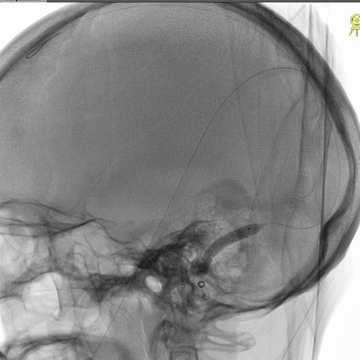

介入治疗后右侧颈动脉造影:上矢状窦、直窦和右侧横窦-乙状窦均见显影,右侧横窦局部狭窄明显。